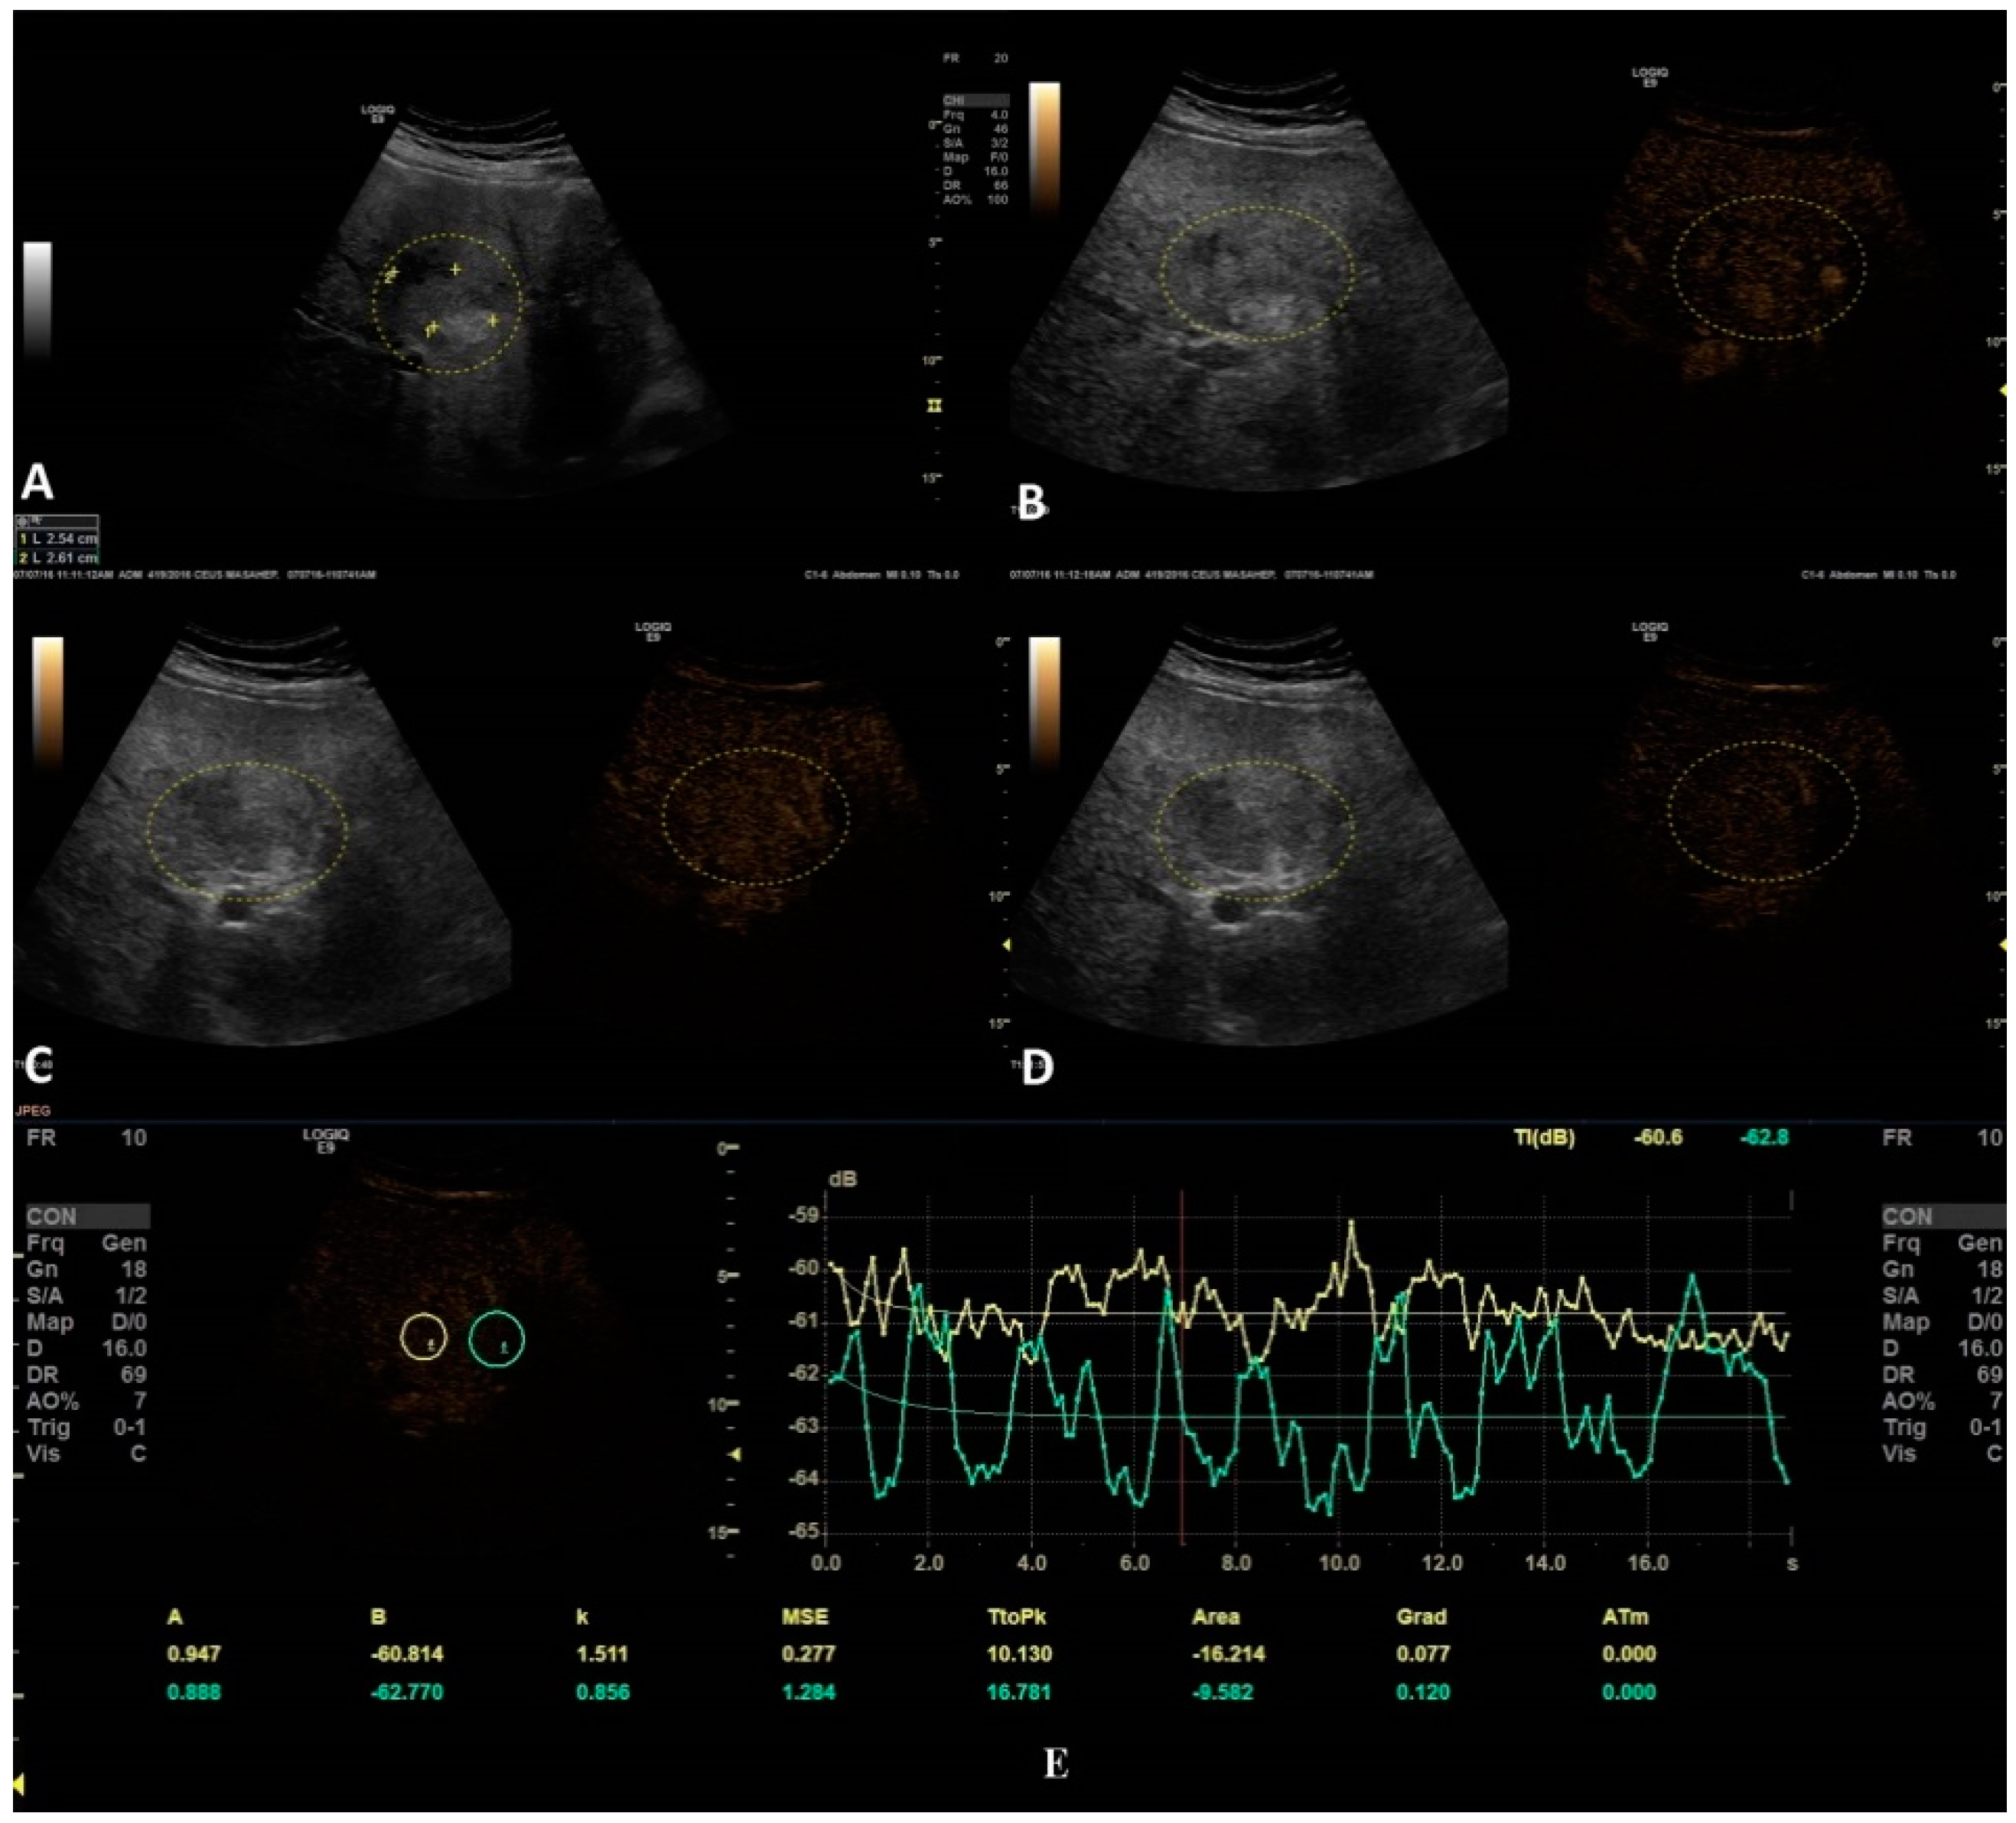

The second step was to quantitatively analyze the tissue perfusion in the late phase of CEUS evaluation using the TIC feature, and to highlight the presence of FLL washout. CEUS examination was performed with the C1-6 convex probe following the CEUS guidelines for the liver. The contrast agent used was SonoVue® (Bracco SpA, Milan, Italy), given as an intravenous bolus of 1.7 mL of SonoVue, followed by 10 mL of saline [1,2]. The late phase (>120 s) of each lesion was reassessed and evaluated via time–intensity curve analysis. The curve fitting parameters for the washout in the bolus injection were time to peak, area under the curve, maximum gradient, and curve gradient, which were evaluated in order to depict the slightest washout phenomena of the lesion. Curve fitting for washout was calculated with the following formula: Washout: F(t) = Aexp(−kt) + B (as explained in Figure 3) [10]. Two regions of interest were selected, one outlining the lesions and the second reference region near the parenchyma, which is possible to perceive at the same depth. All of the lesions’ washout phases were evaluated using TIC.

The only TIC-CEUS parameter that showed significant differences between malign and benign lesions was AREA (−25.08 ± 37.98 and −7.08 ± 42.6, p = 0.04). The parameter AREA is in fact the area under the curve. The curve fitting algorithm is applied and a curve is obtained according to the intensity observed. Some examples of fitted curves are shown in both Figure 4a,b, where parameter AREA is the area under the fitted curve. Since the washout is characterized by a smaller intensity of activity, the observed curve will fall and hence the fitted curve will fall, too. This fact leads to a smaller AREA parameter. This phenomenon allows us to impose a threshold on the AREA parameter in order to detect the washout. We also tested A (the difference between B and the intercept intensity at t = 0), B (the minimum intensity at t = infinity), k (the gradient at t = 0, calculated by “−A*k”), TtoPk (time to peak intensity from the start frame to the end frame), but without any statistical significance (all p-values > 0.05) (Table 3).

Figure 4. In this setting, a benign lesion was assessed, as depicted in B-mode in frame (A). In frames (BD) are depicted the vascular arterial, portal, and late phases of CEUS with different enhancement characteristics, respectively. In frame (D), the enhancement pattern is not recognizable; thus, TIC analysis (E) was applied. The results did not show us any objective washout phenomena (the graphs are not intersecting one another).